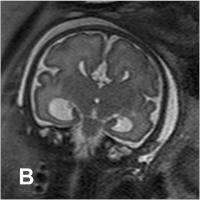

Abbildung 2a-b: SSW 30, Fetus mit Balkenagenesie, A. Medianes Schnittbild: Fehlender Balken, radiäre Gyrierung an der Medialfläche der Hemisphäre. Der Aquädukt und die Vierhügelplatte unauffällig. Der Hirnstamm zeigt dorsal dünklere Signale als ventral, was der normalen, dort bereits in dieser SSW vorhandenen Myelinisierung entspricht. Im Profil geringe Retrognathie. B. Frontales Schnittbild. Typische Konfiguration der Seitenventrikel, die auf Grund der medial der Vorderhörner erkennbaren Probst’sche Bündel weit auseinander stehen. In den erweiterten Temporalhörnern erkennt man eine nahezu senkrecht stehende Hippocampusformation, was einer Malrotation entspricht. Die Gyrierung ist symmetrisch, eine pathologische Konfiguration des frontalen Anteils des Gyrus cinguli, wie sie im Rahmen der Balkenagenesie zu erwarten ist, besteht. Intrazerebral ist die zelldichtere und daher dünklere Stammganglienregion von der helleren weißen Substanz, die ebenfalls in entwicklungsbedingt unterschiedliche Graustufen gegliedert ist, abgrenzbar.